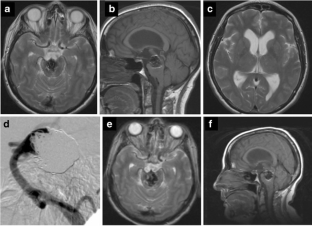

Fig. 1

Fig. 2